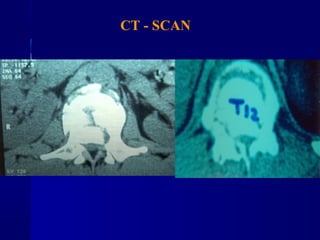

CT - SCAN

 AANN.. PPEERR..

 FF –– 2222 yyrrss

 FFaallll

 LLeevveell :: TT1122

 TTyyppee :: AA33..33

 AA..SS..II..AA.. :: EE